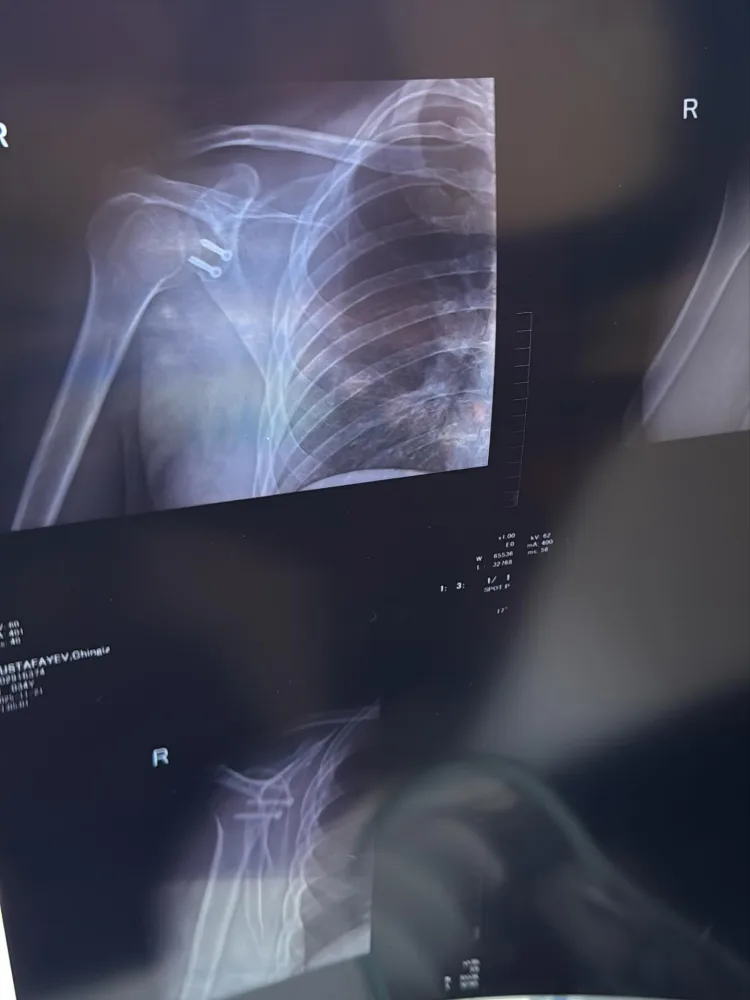

Avroviziya təmsilçimiz Çingiz Mustafeyav əməliyyat olunub.

OLAY yazır ki, bu barədə o, özü məlumat yayıb. Sənətçi uzun müddətdir yaşadığı bir problemi aradan qaldırdığını bildirib:

“5 il ərzində çiynim 7 dəfə çıxıb. Hər dəfə eyni ağrı, eyni qorxu, eyni narahatlıq… İdman da, aktiv həyat da tam mümkün olmurdu. Hər dəfə özümə deyirdim: “hələ tezdir, bir az da gözləyim bir söznən iş güc və sairə…” Amma 2 ay əvvəl sonuncu dəfə çiynim çıxanda anladım ki, artıq bu məsələni həll etməyin vaxtı gəlib.

Qərar verdim və sağlığımı ürəyimə yatan, ilk görüşdən etibarımı qazanan həkimə həvalə etdim və nəhayət dünən əməliyyat olundum. İndi uzun bir reabilitasiya dövrü başlayır. Əməliyyat önəmlidir, amma ən çətini — sonraki mərhələdir: səbir, intizam və özünü qorumaq. İstəyiram biləsiniz ki dualarınız və dəstəyiniz mənə böyük güc verir.  Eyni problemi yaşayan dostlara isə bir sözüm var: Gözləməyin. Mənim kimi illərlə səbr etməyin. Hər çıxıq çiyni daha çox zədələyir.

Vaxtında əməliyyat — gələcək həyatınızı xilas edir”.